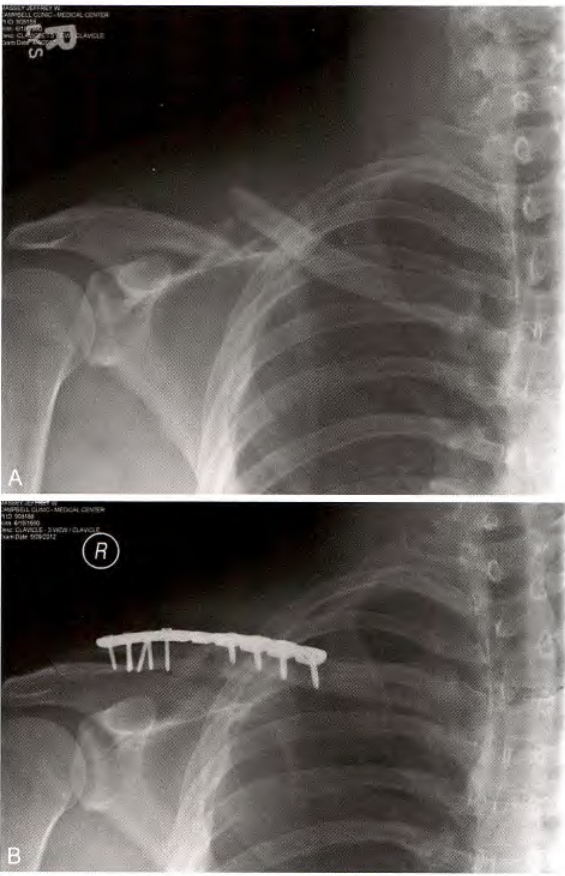

A. 锁骨骨折, B髓内钉治疗

使用带尾帽远端有螺纹的髓内钉固定(Rockwood 锁骨钉)

髓内钉固定改良版(锁骨中段骨折)

1、交锁髓内钉固定

半沙滩椅位,从骨折线外侧切开一个5-7cm切口,显露骨折线后扩髓。使用t型手柄,通过后外侧孔旋转插入直径最大且长度合适的钉子。用2.5 mm的钻头将导杆固定在钉的外侧锁孔上。

(a, b)一名38岁男性左侧锁骨粉碎性骨折术前及术后8周前后位X光片;(c, d)术后2年骨折愈合后前后位X光片,显示创伤后短缩6.3%;(e)同一患者的临床图像。